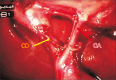

Results: Of the 375 patients, 26 (6.9%) had laparoscopic anatomical variations, of whom 19 (73.1%) had vascular variations and seven (26.9%) had ductal variations. The anatomical variations included the following: double cystic artery of separated origin, seven cases (26.9%); Moynihan's hump, six (23.1%); double cystic artery of single origin, four (15.4%); thin long cystic duct, four (15.4%); subvesical duct, three (11.5%); and cystic artery hocking the cystic duct, two (7.7%).

Conclusion: Biliary anatomical variations can be expected in any dissected zone. Most of the detected variants were associated with the cystic artery. An overlooked accessory cysto-biliary communication can cause complicated biliary leakage. A surgeon's skills and knowledge of laparoscopic anatomical variants are essential for performing a safe laparoscopic cholecystectomy.